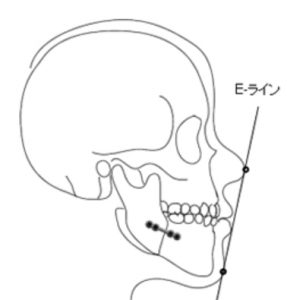

◉横顔での唇や頬のライン

セファロレントゲンでは、主に骨や歯といった硬組織を写し出します。しかし頬や唇といった軟組織もある程度写るため、横顔のラインをみる目安にもなります。

例えば、唇がどのくらい前に出ているのか、横顔の美しさの基準となるE-ライン(エステティックライン)はどうかを見ることができます。